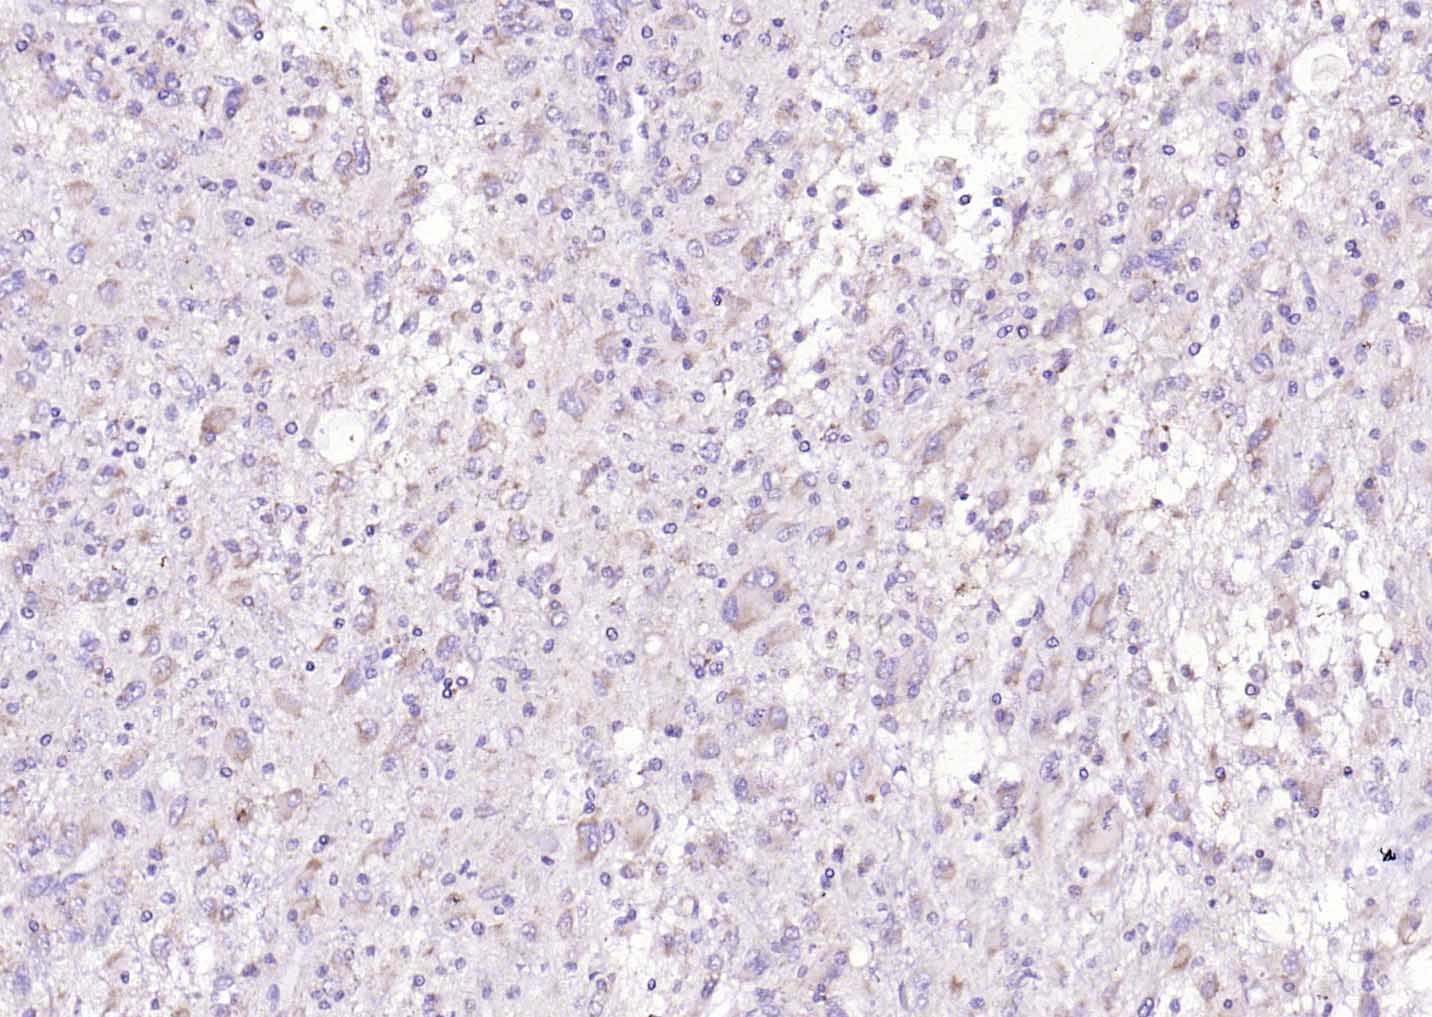

Paraformaldehyde-fixed, paraffin embedded (Human glioblastoma); Antigen retrieval by boiling in sodium citrate buffer (pH6.0) for 15min; Block endogenous peroxidase by 3% hydrogen peroxide for 20 minutes; Blocking buffer (normal goat serum) at 37°C for 30min; Antibody incubation with (phospho-Tau (Thr217)) Polyclonal Antibody, Unconjugated (bs-2843R) at 1:200 overnight at 4°C, followed by operating according to SP Kit(Rabbit) (sp-0023) instructionsand DAB staining.